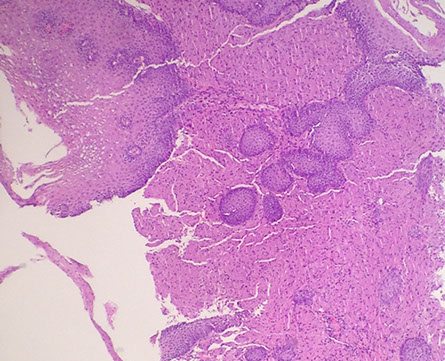

Squamous Papilloma

Uncommon, usually incidental, in distal esoph, whites, F>M, assoc irritation, grossly tiny white warty nodule(s)

- may be assoc c dysplasia (not common)

- may be 2/2 reflux or HPV, controversial

- micro: bland polypoid squamous mucosa c fibrovascular core